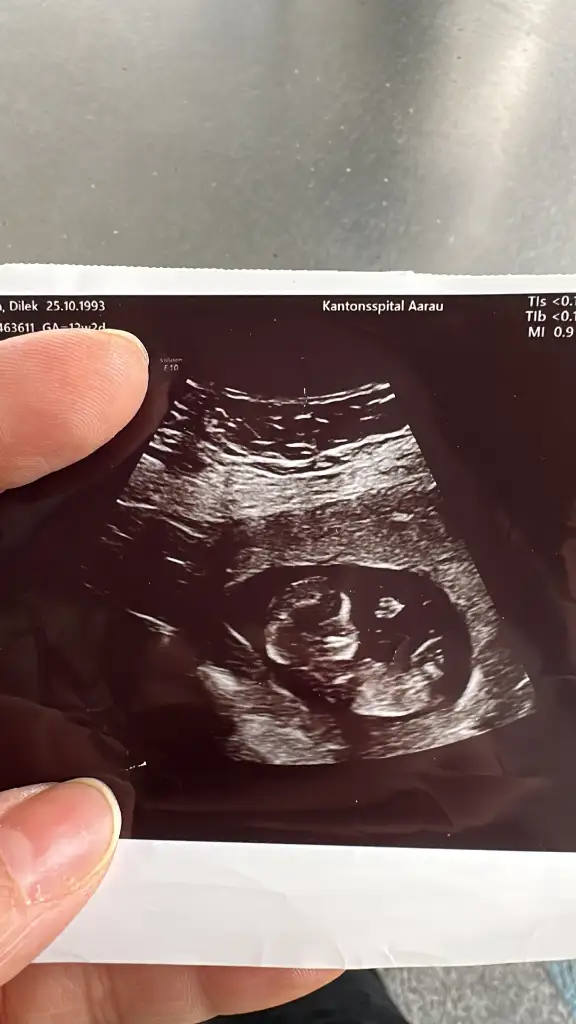

Lütfen bana da bir yorum yapar mısınız. Karından. 13+4 haftalık. İki kızım var erkek olsun istiyorum 🙈

Eklentiler

• IMG_20250307_073925.webp

IMG_20250307_073925.webp

22,9 KB · Görüntüleme: 150